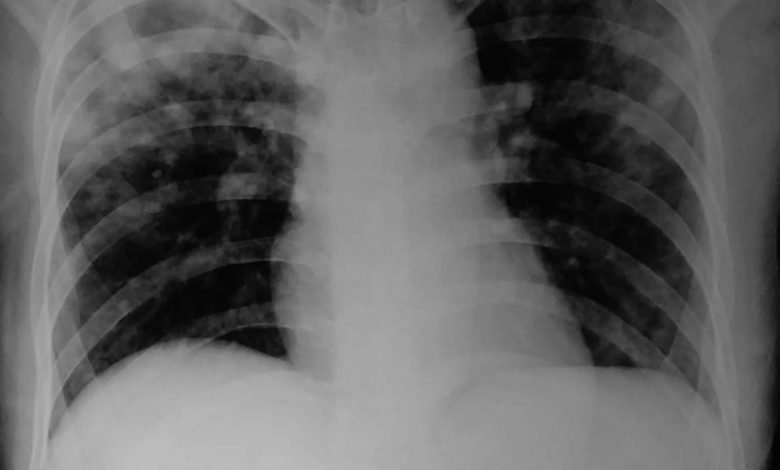

उत्तर प्रदेश औरैया जिला क्षय रोग अधिकारी डॉ. संत कुमार ने बताया कि फेफड़े की टीबी को पल्मोनरी और शरीर के अन्य हिस्से की टीबी को एक्स्ट्रा पल्मोनरी टीबी कहा जाता है। टीबी के मरीजों में करीब 70 फीसदी में पल्मोनरी और 30 फीसदी में एक्स्ट्रा पल्मोनरी टीबी होती है। एक्स्ट्रा पल्मोनरी टीबी से ग्रसित मरीजों से दूसरों को खतरा कम होता है, जबकि पल्मोनरी टीबी दूसरों को ज्यादा संक्रमित कर सकता है। एक्स्ट्रा पल्मोनरी टीबी जिसे होता है, उसे सूजन, दर्द, हल्का बुखार, रात में पसीना, भूख नहीं लगती है। डॉ.कुमार ने बताया कि एक्स्ट्रा पल्मोनरी टीबी पल्मोनरी टीबी के साथ भी हो सकती है। इस प्रकार की टीबी अधिकतर कमजोर प्रतिरोधक क्षमता वाले लोगों और छोटे बच्चों में अधिक पायी जाती है। एचआईवी से पीड़ित लोगों में, एक्स्ट्रा पल्मोनरी टीबी की संभावना अधिक होती है। एक्स्ट्रा पल्मोनरी टीबी को अंगों के हिसाब से नाम दिया गया है। मुख्यत: हड्डी, रीढ़ की हड्डी, आंत, गले की कंठमाला और फेफड़ों में पानी का उतर आना एक्स्ट्रा पल्मोनरी टीबी की श्रेणी में आते हैं।

जिला कार्यक्रम समन्वयक श्याम कुमार ने बताया कि वर्ष 2022 में जनवरी माह से नवम्बर माह तक 1657 लोगों में एक्स्ट्रा पल्मोनरी टीबी की पुष्टि हुई है ।

जिला पीपीएम समन्वयक रविभान सिंह ने बताया कि दो सप्ताह या अधिक समय तक खांसी आना, खांसी के साथ बलगम आना, बलगम में कभी-कभी खून आना, सीने में दर्द होना, शाम को हल्का बुखार आना, वजन कम होना और भूख न लगना सामान्य लक्षण हैं। ऐसे लक्षण मिलने पर तत्काल जांच कराएं।